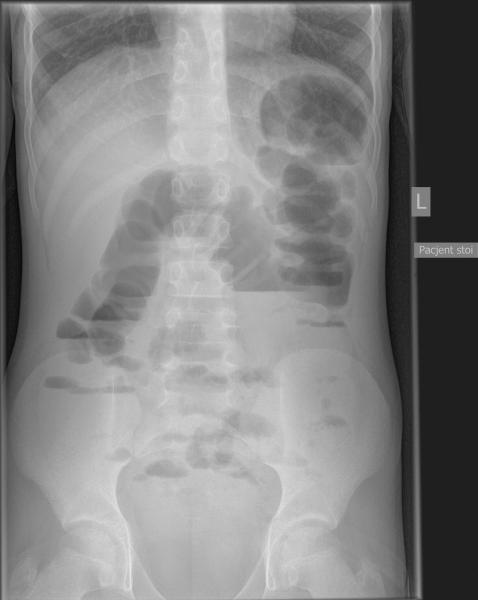

Przypadek 4: 11-letni chłopiec z napadowymi bólami brzucha od 3 tygodni, z wielokrotnymi wymiotami. Pacjent ani rodzice nie potrafili określić kiedy było ostatnie wypróżnienie. Podejrzenie niedrożności przewodu pokarmowego.

Rozpoznanie: Liczne poziomy płynu w dystalnych pętlach jelita cienkiego oraz w miernie rozdętym jelicie grubym do wysokości zstępnicy, brak powietrza w rzucie odbytnicy - cechy niedrożności. Bez cech perforacji.